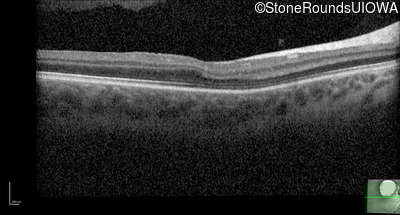

Age at visit: 2 months (Visit 3)